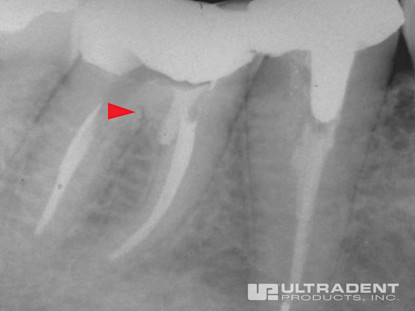

Etkili Perforasyon Onarımı

Mesial bukal kanalın servikal üçüncü kısmında yer alan perforasyon.